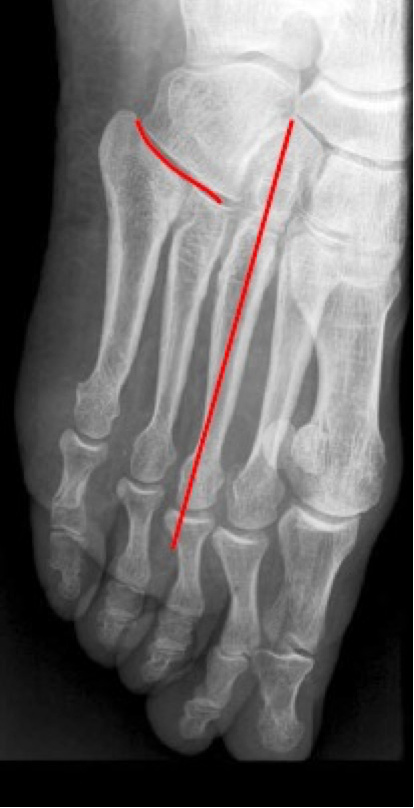

A tangent placed along the medial border of the medial cuneiform should intersect the base of the first metatarsal. In the case of medial TMT instability with forefoot abduction stress, this tangent passes medial to the base ("medial column sign" positive) (Fig. 15).

Similar to this technique, the stability of the ligamentous connections can be assessed using a dynamic radiographic stress test. Coss et al (28) demonstrated that the displacement of the medial column line was due to incompetence of the Lisfranc ligament combined with the dorsal TMT ligament. The positions of the base of the second metatarsal on the AP projection and the fourth metatarsal on the oblique projection are the main indicators of instability of the TMT complex. However, the importance of using weight-bearing radiographic studies in this context must be emphasised. Shapiro et al (29) provided evidence of the insufficient validity of unloaded images compared to analysis of loaded radiographic images in distinguishing stable and unstable TMT lesions. (Fig. 16)